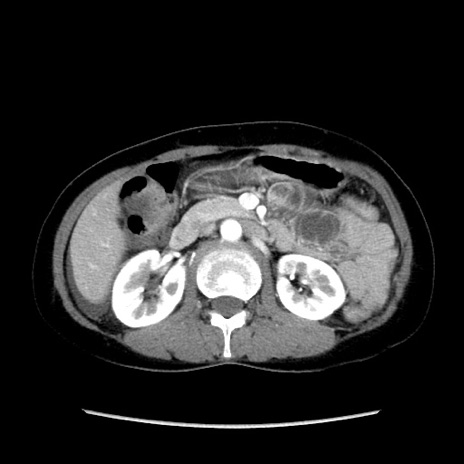

症例32(横断像)

【症例】40歳代 女性

【主訴】上腹部痛、嘔気・嘔吐

【現病歴】約9時間前頃から急に上腹部痛、嘔気、嘔吐が出現。改善しないため救急要請。

【既往歴】子宮頚癌(広汎子宮全摘術、放射線療法)、腸閉塞

【身体所見】腹部:平坦、軟、腸雑音亢進、上腹部を中心に腹部全体に圧痛あり。

【データ】WBC 8400、CRP 0.03